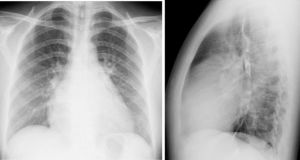

(2)X線檢查可以了解心臟大小和肺部的改變。